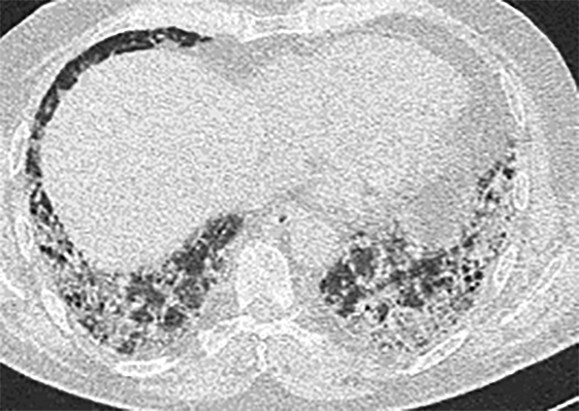

- Radiomorphologisch findet man bei einer akuten Exazerbation einer bestehenden Lungenfibrose Milchglasverschattungen, teilweise auch Konsolidierungen auf dem Boden fibrotischer Veränderungen (Abb. 36.3a). Bei einer akuten interstitiellen Pneumonie (AIP), die sich klinisch ähnlich äußert, fehlen die fibrosierenden Veränderungen (Abb. 36.3b).

Abb. 36.3 Radiologie bei akuter Exazerbation einer idiopathischen Lungenfibrose (IPF) und akuter interstitieller Pneumonie (AIP).

In beiden Fällen sieht man ausgedehntes Milchglas, jedoch nur bei der IPF auch das „UIP-Muster “mit den Honigwaben und Traktionsbronchiektasen).

a HRCT eines Patienten mit akuter Exazerbation einer IPF. (Quelle: Prof. Heußel und Prof. Kreuter, Thoraxklinik Heidelberg)

b HRCT eines Patienten mit AIP. (Quelle: Prof. Heußel und Prof. Kreuter, Thoraxklinik Heidelberg)